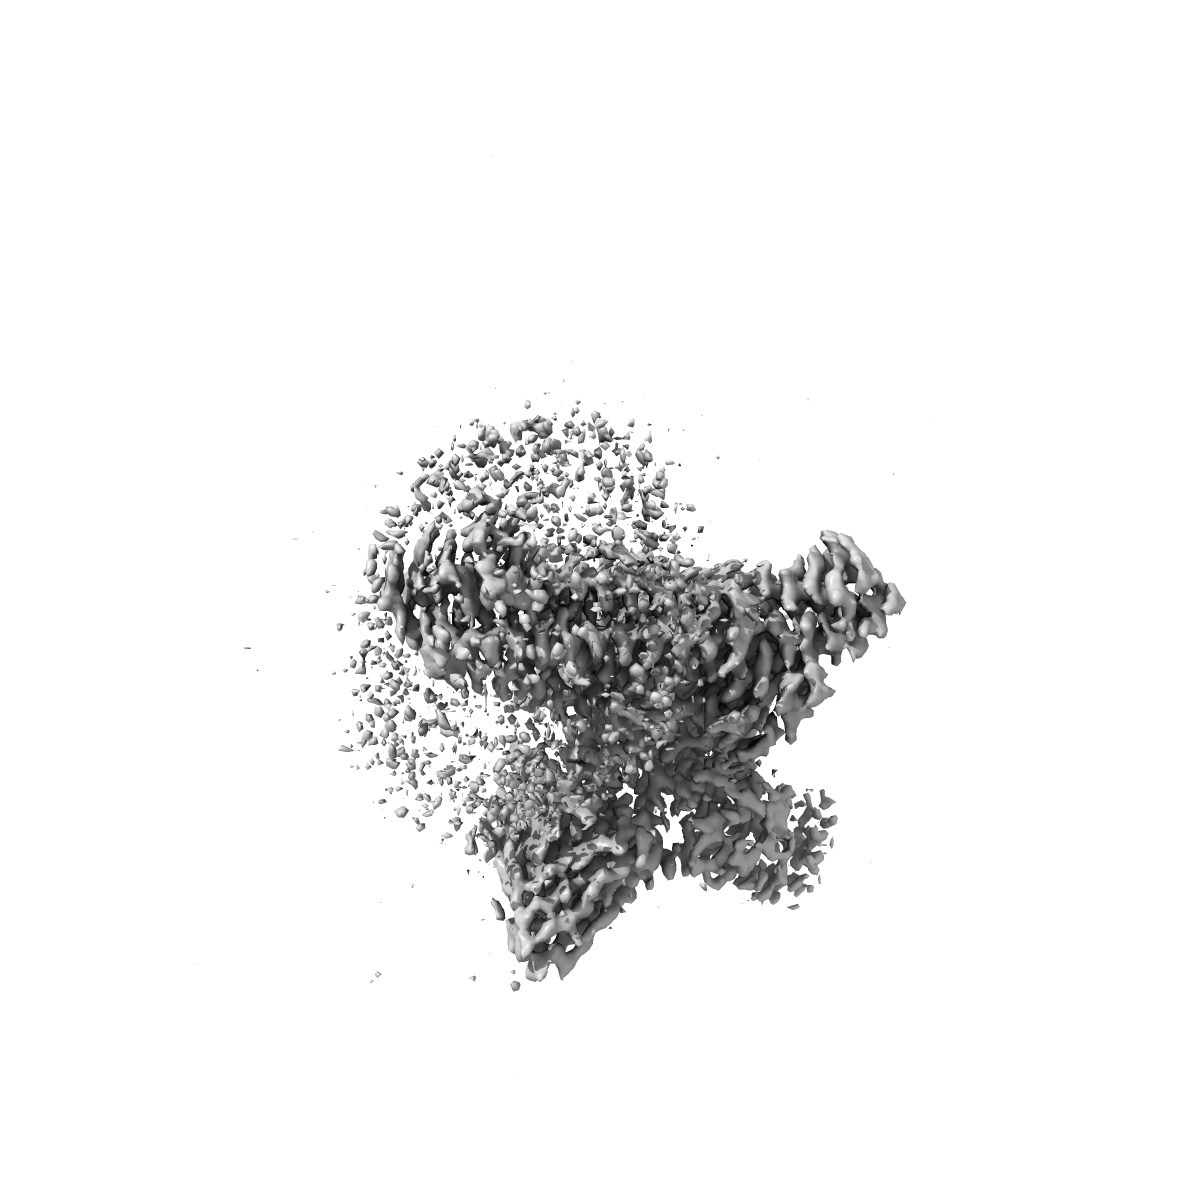

CryoEM structure of somatostatin receptor 4 (SSTR4) in complex with Gi1 and its endogeneous ligand SST-14

Sample: Complex structure of somatostatin receptor 4 (SSTR4) in complex with Gi and its endogeneous ligand SST-14

Fitted models: 7xms